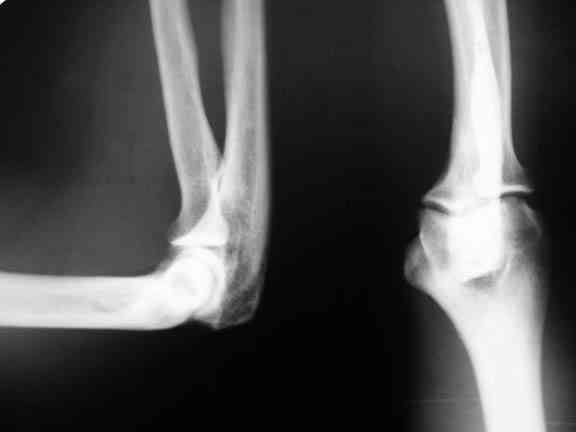

Извиняюсь, что не уточнил. На рентгенограммах второй руки абсолютно идентичная картина.

А где анамнез? Были ли моменты физической перегрузки конечностей на протяжении последних трех-четырех недель (спортзалы,переноска тяжелых предметов и т.д)? Локальный остеопороз в месте прикрепления сухожилий часто неспецифичен и просто отражает наличие воспаления. Предварительный диагноз - синдром перегрузки трицепса (инсерционит, тендинит, тендинопатия... - choose yourself). Если анамнез подтверждается, то мой выбор - двухсторонняя блокада стероидом+анестетик, эластическое бинтование (локоть 90 гр.), а при односторонних поражениях 10-дневная гипсовая иммобилизация; физпроцедуры, в подостром периоде ЛФК на макс.пассивное сгибание в локтевом с-ве. Если через два дня не будет улучшения, можно сделать КТ, хотя я сомневаюсь в его информативности для этой зоны.

Уважаемый коллега! Это заболевание из группы т.н.энтезопатий - по типу "теннисного локтя", отличные результаты лечения дает метод ударно-волновой терапии аппаратом "DORNIE EPOS-ULTRA" производства Германии. Как лучевой диагност, КТ проводить не советую, т.к. уточнять здесь нечего, пустая трата денег. По рентгенограммам даже обызвествлений в обл. локтевого отростка не определяется. С уваж. Е.М.(инкогнито)